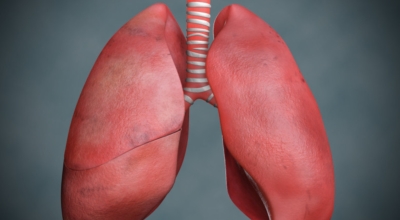

폐렴은 폐의 세기관지 이하 부위 특히나 폐포에 발생한 염증입니다. 폐렴을 유발하는 병원 미생물은 우리의 생활환경에 존재하고 있고 몸 안에 서식합니다. 폐렴의 가장 흔한 까닭은 미생물인 세균이나 바이러스이고, 드물게 곰팡이에 의한 감염이 있을 수 있습니다.

미생물에 의한 감염성 폐렴 이외에 화학물질이나 구역질물과 같은 찌꺼기의 흡인, 가스의 흡인, 방사선 치료 등에 의해 비감염성 폐렴이 발생할 수 도 있어요. 폐렴구균은 노인을 감염시키는 세균으로 가장 많이 알려져 있죠. 그리고 폐렴은 일상적인 예방이 중요합니다. 손씻기, 양치질, 구강 케어 등을 습관화하고 주변 환경을 깨끗하게 해주고 위생 관리를 해서 폐렴을 방지할 수 있답니다.